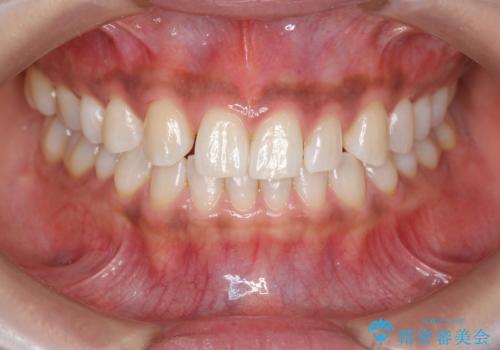

前歯のがたつき 過蓋咬合